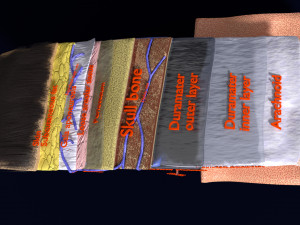

Brain with meninges scalp detailed labelled 3D 3D मॉडल

A blend model of brain along with its covering layers (meninges), skull bone and scalp labelled in detail and anatomically precise. The parts depicted are white, gray, pia, arachnoid, dura, bone, skin, fat, aponeurosis, periosteum, falx cerebri and more.

The material is high resolution image textures and normal maps based on non overlapping UVs. The texture and normal maps are packed with the blend file itself.